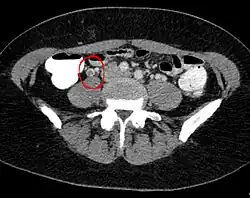

Ovarialvenenthrombose in der Computertomographie: Man erkennt einen umspülten, im Vergleich zum kontrastierten Blut etwas dunkleren Thrombus in der rechten Ovarialvene (im Bild links).